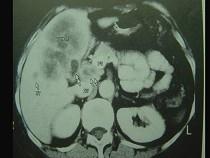

问题 患者,女,51岁,右上腹隐痛1月余,CT扫描如图,最可能的诊断是()

选项 A.胆囊癌(肿块型)侵犯肝脏 B.肝癌侵及胆囊 C.肝转移瘤 D.胆囊周围肝脓肿 E.肝血管瘤

答案 A